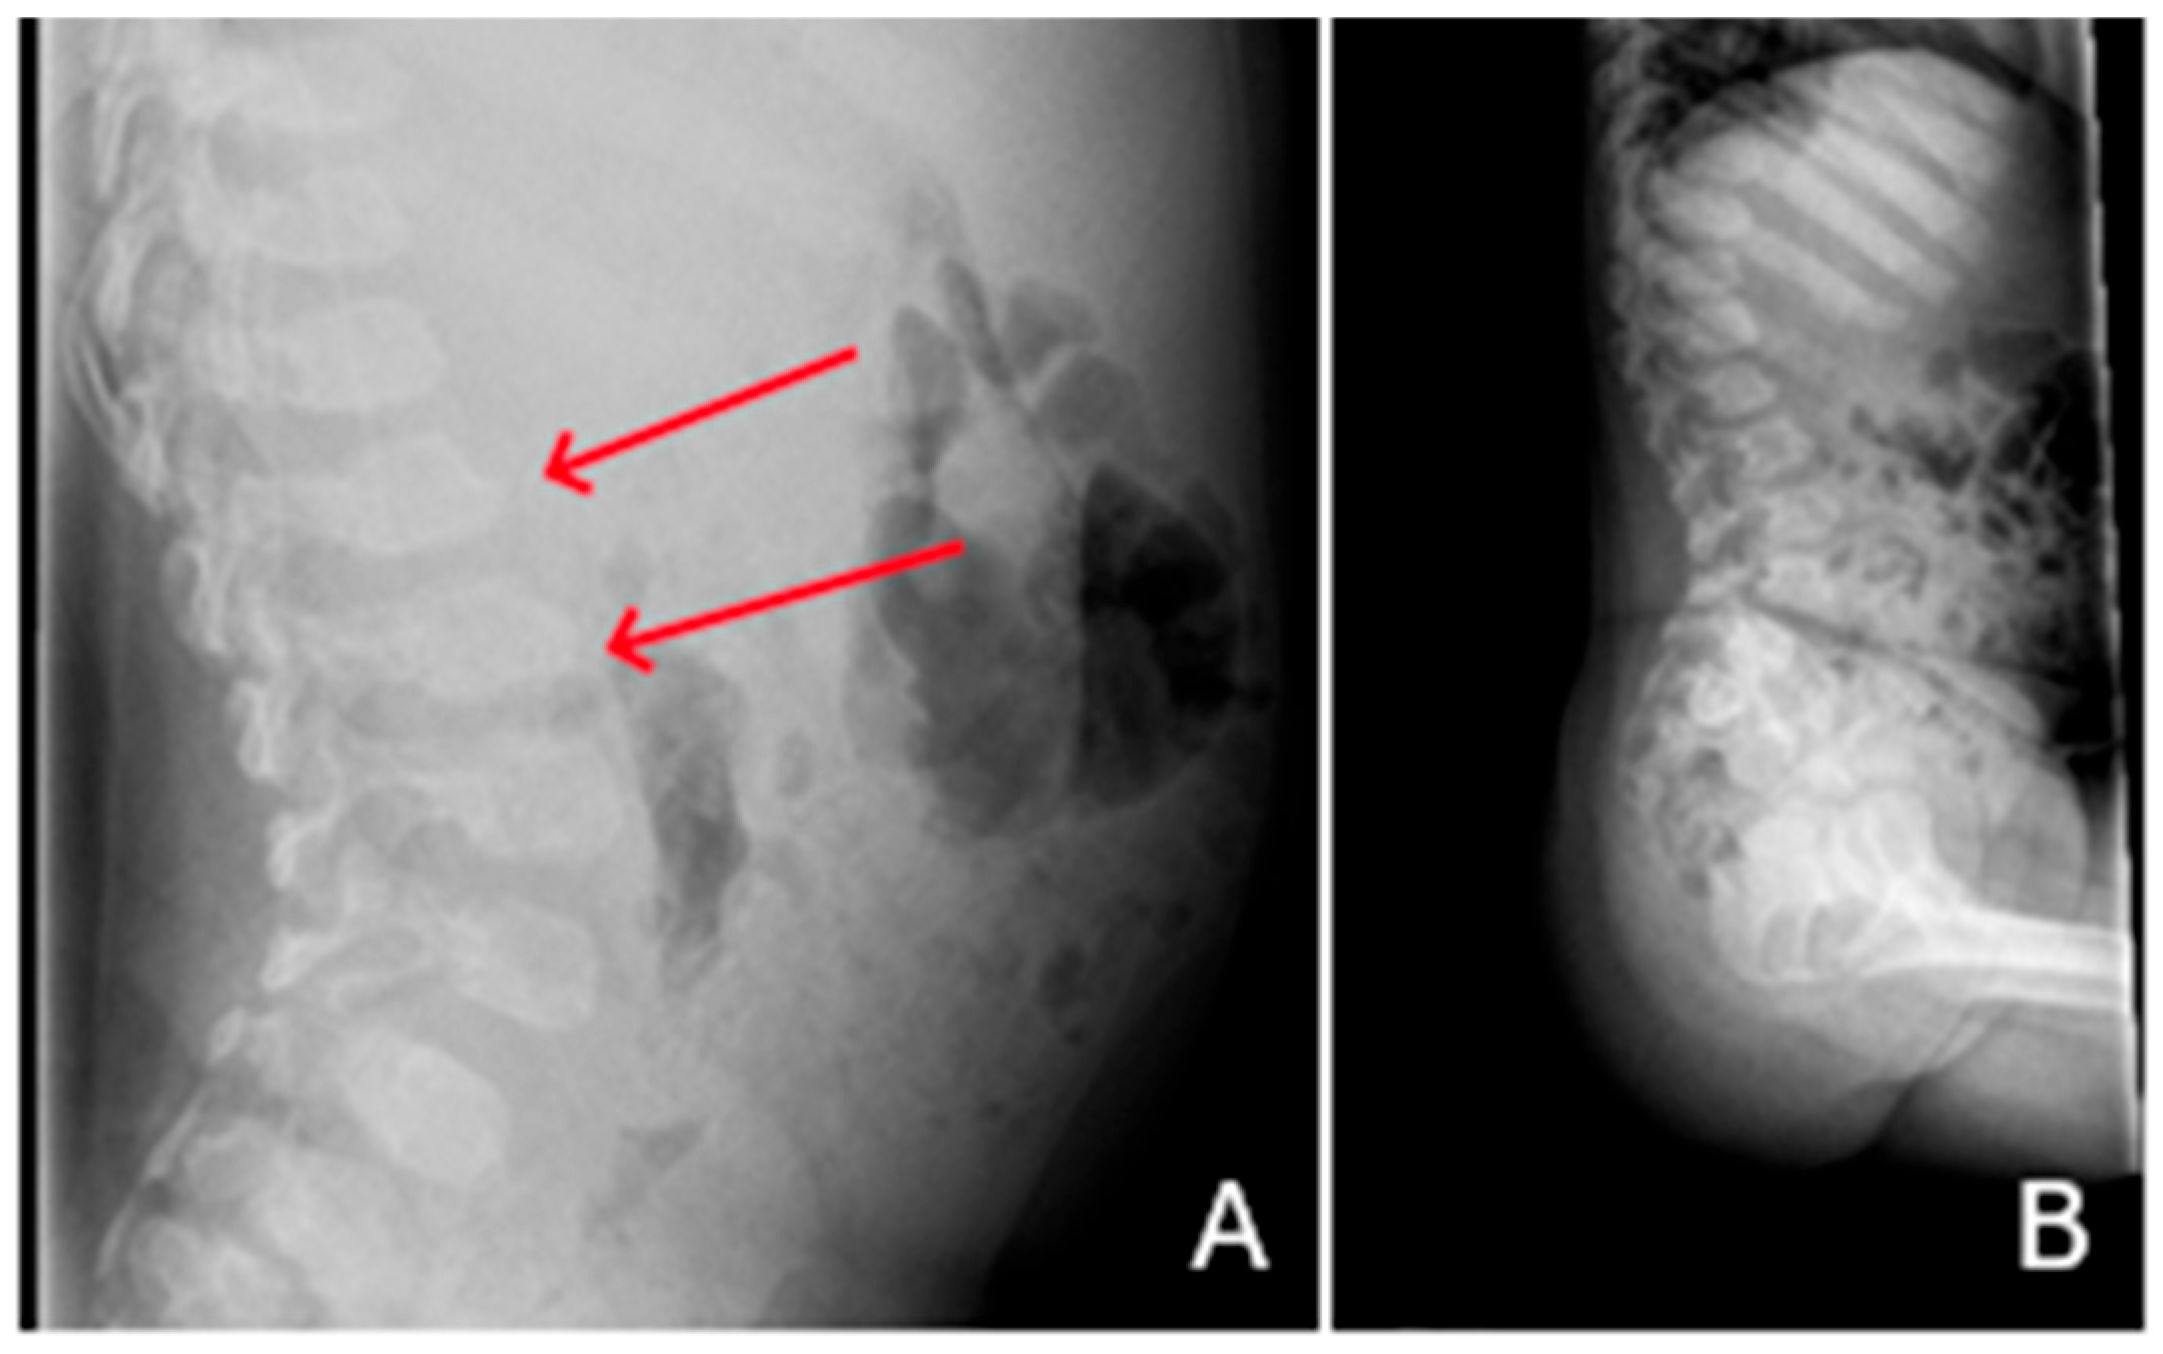

| P2 (MPSII) | Baseline | RX and MRI | Spine | Vertebral body deformities; posterior bulging of the intervertebral discs. |

| After 6 years of ERT | RX and MRI | Spine | Thoracolumbar kyphosis; anterior beaking and posterior scalloping of vertebral bodies. | |